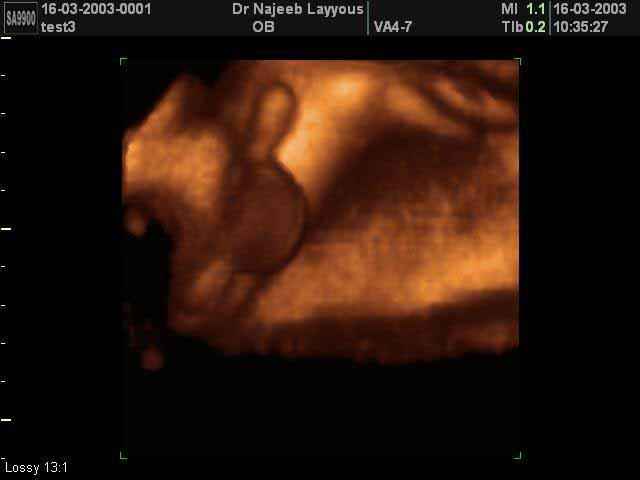

- 3D Photos échographie des parties du fœtus